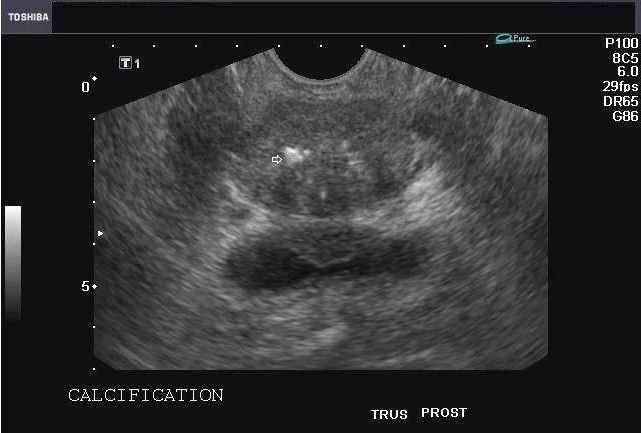

上海一妇婴江宁东医生:前列腺结晶、钙化和结石,是什么东东?

二、前列腺结晶、钙化、结石的形成:

如果男性长期没有性生活或者没有排精,或者有局部炎症时,这是前列腺液就会不能通畅的排出,拥堵在管道内,前列腺液内容物会析出、沉淀,形成小结晶。或者男性憋尿造成尿液返流到前列腺内,也可能导致尿液中的结晶在前列腺腺管内。小的结晶会渐渐形成核心,析出的物质包裹在其周围,形成前列腺结石。另一方面,由于憋尿等因素,尿液通过后尿道精阜,从前列腺的开口处反流进入前列腺腺管,也尿液中的物质沉淀形成核心阻塞腺管,进而形成结晶、钙化、结石。